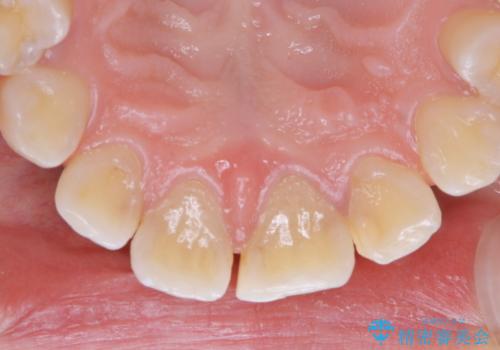

プラーク(細菌の塊)や歯石がたまると歯の表面はザラつきいてきます。そのザラつきは歯周病や虫歯菌の棲家となります。そのまま放置すると、歯肉が腫れてきたり、歯肉から出血したり、口臭が強くでたりします。とくに歯肉の境目は、歯磨きで汚れを除去することが難しく、プラーク(細菌の塊)や歯石が溜まりやすい場所です。

歯並が、がたついている場合はなおさら汚れが溜まりやすいです。矯正治療前や矯正中、定期的にPMTCをすることで、矯正治療中の歯肉トラブルを防ぐことにつながります。